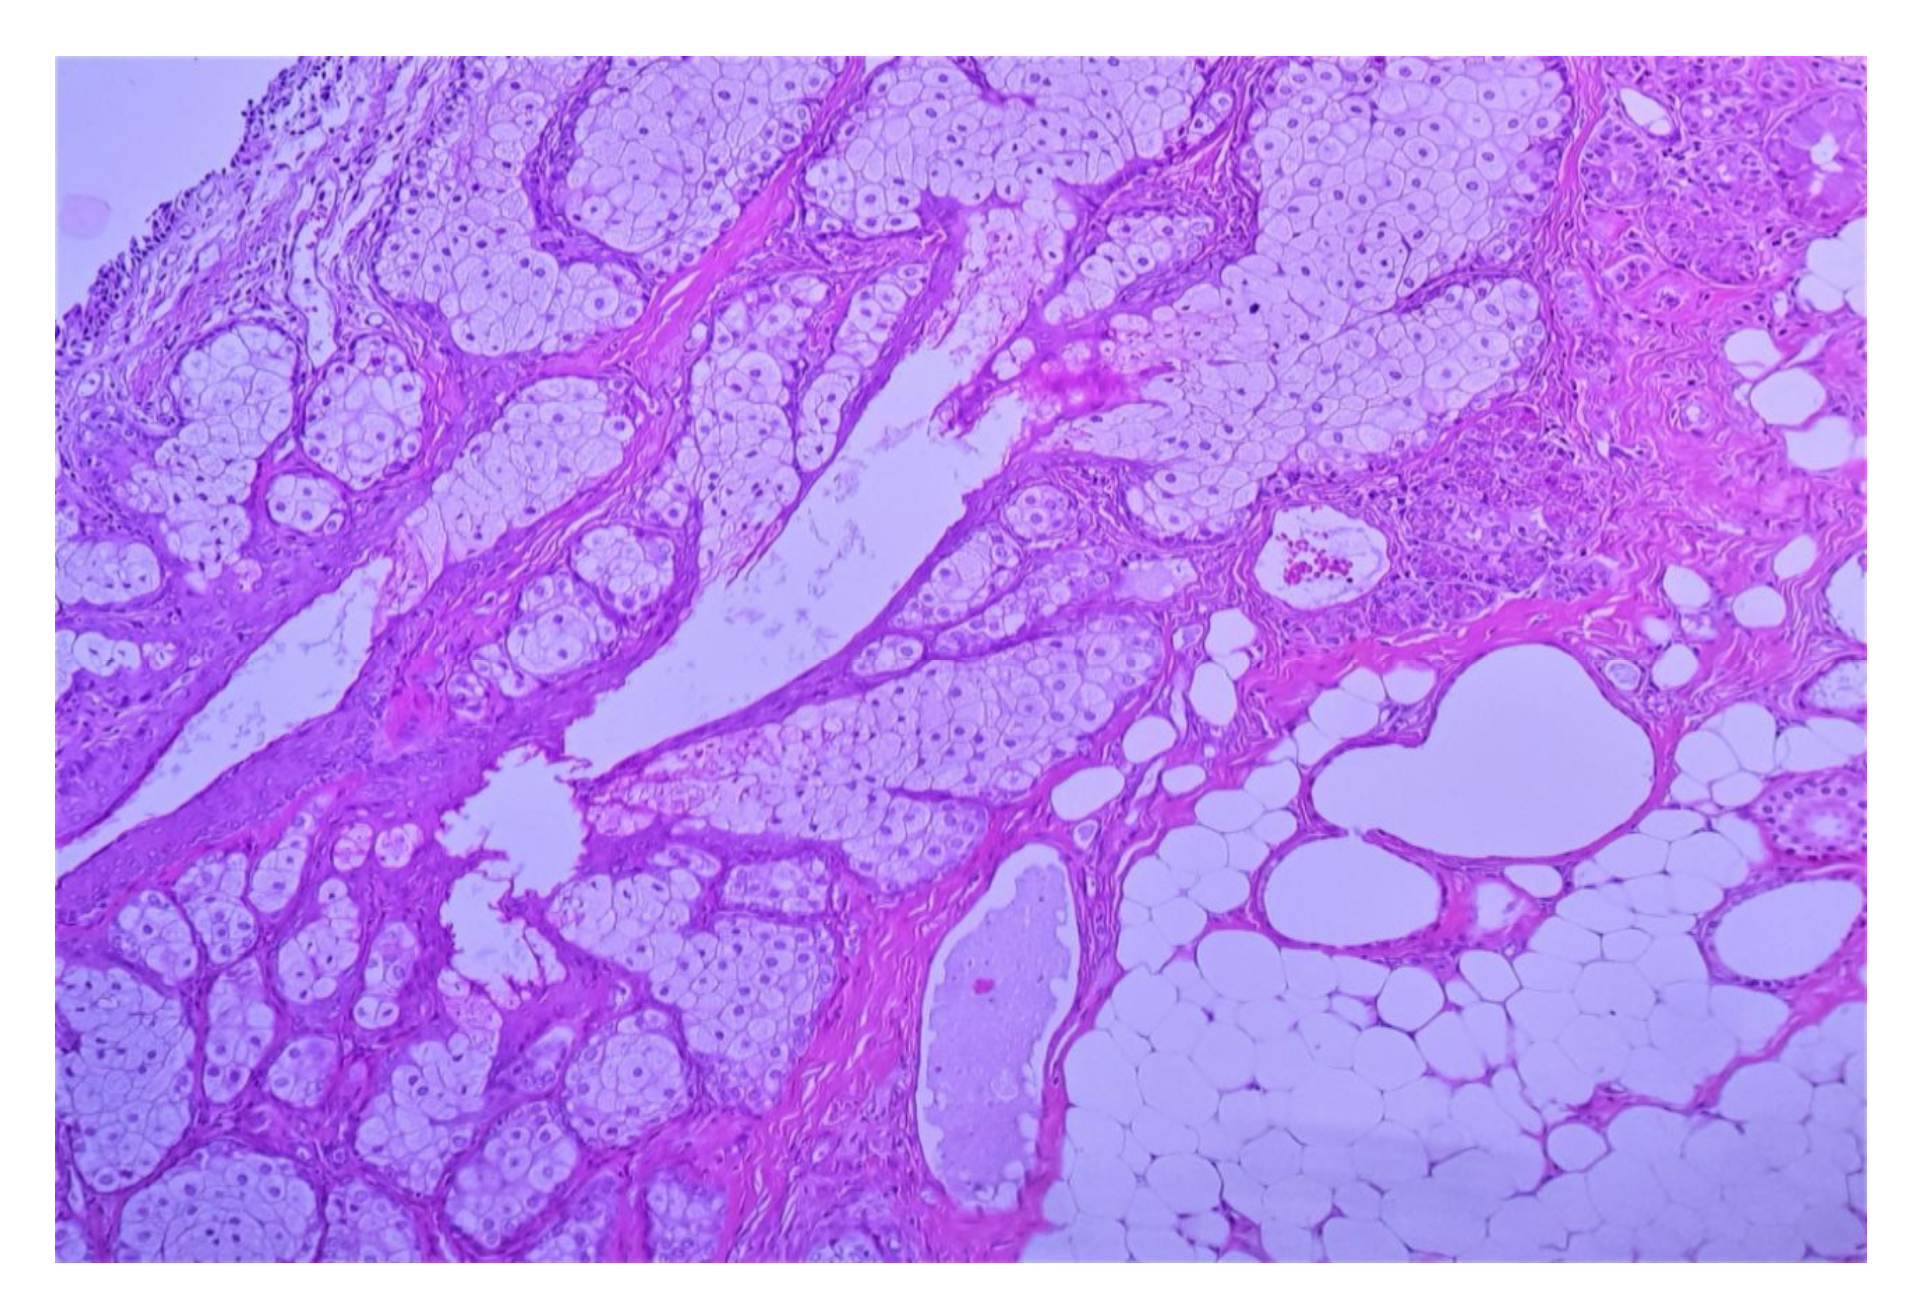

2.7. Struma Ovarii

2.7.1. Macroscopic Features

2.7.2. Microscopic Features